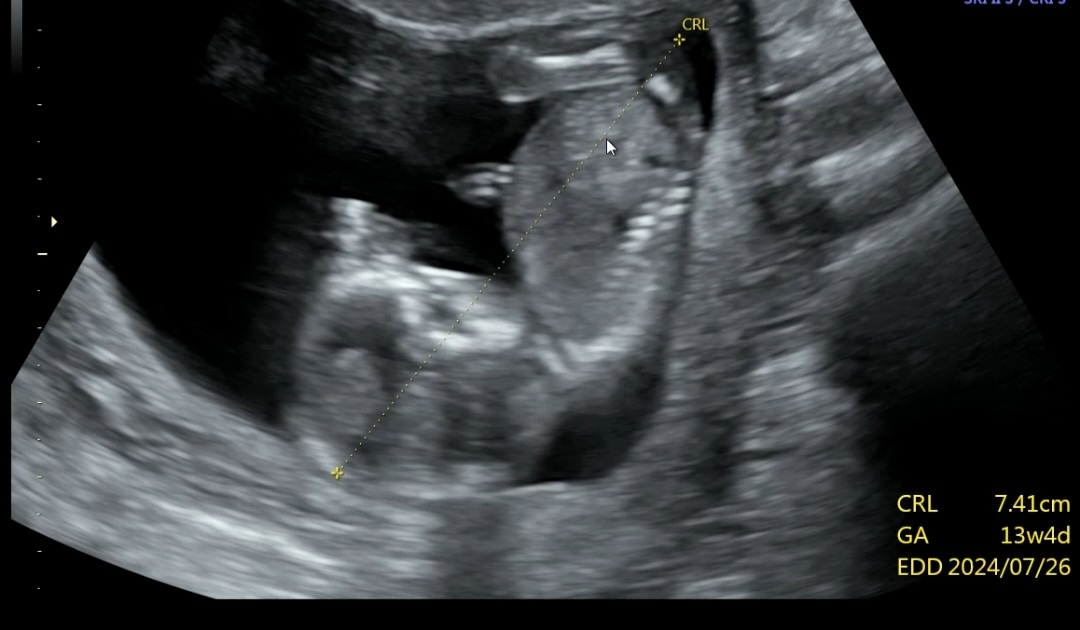

13주 4일째인데..딸을 너무갖고싶은 엄마입니다. 어제 원장님이 말실수인지 ㄲㅊ 라는 말을했는데..딸 가능성 있을까요?